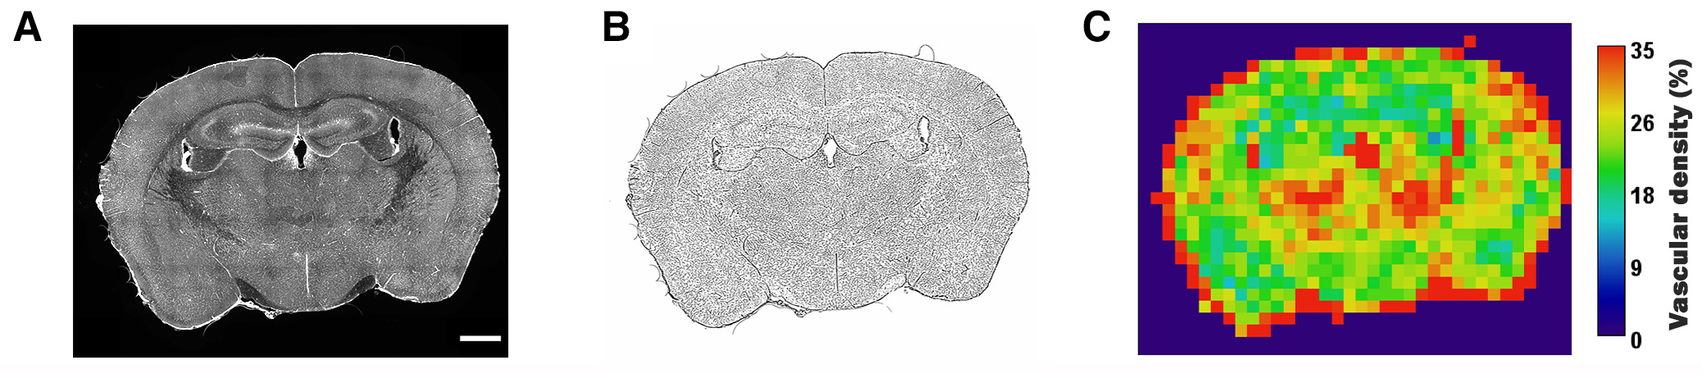

To create a visual readout of the tissue density, Q-VAT creates average tile-wise output maps for all measurements (Figure 6). In the previous sections, we have always performed the quantification on the original acquisition tiles. However, Q-VAT can also be performed on tiles with a different size. The tile-wise output maps offer a clear and simple way to visually represent the quantified morphological read-outs. Figure 6C shows an example of a tile-wise output map of the vascular density quantification of an entire rat brain section with a spatial resolution of 300 × 300 µm. There are several edge effects that should be considered when generating such tile-wise maps. One should be aware that partial volume effects will occur at the edges of the tissue (e.g., periphery and ventricles). Furthermore, non-specific staining at the edges of the tissue can occur due to peripheral drying, under fixation or buildup of secondary antibody (Figure 6A). These edge effects will introduce miscalculations at the edges of the sample (Figure 6C).

Figure 6

Example of a tile-wise morphological output map. (A) Original stitched high resolution images (scalerbar 1000 µm), (B) Vascular mask, (C) Tile-wise output map of vascular density expressed in percent of tissue of the entire rat brain section. Area outside the brain tissue was set to pure black.